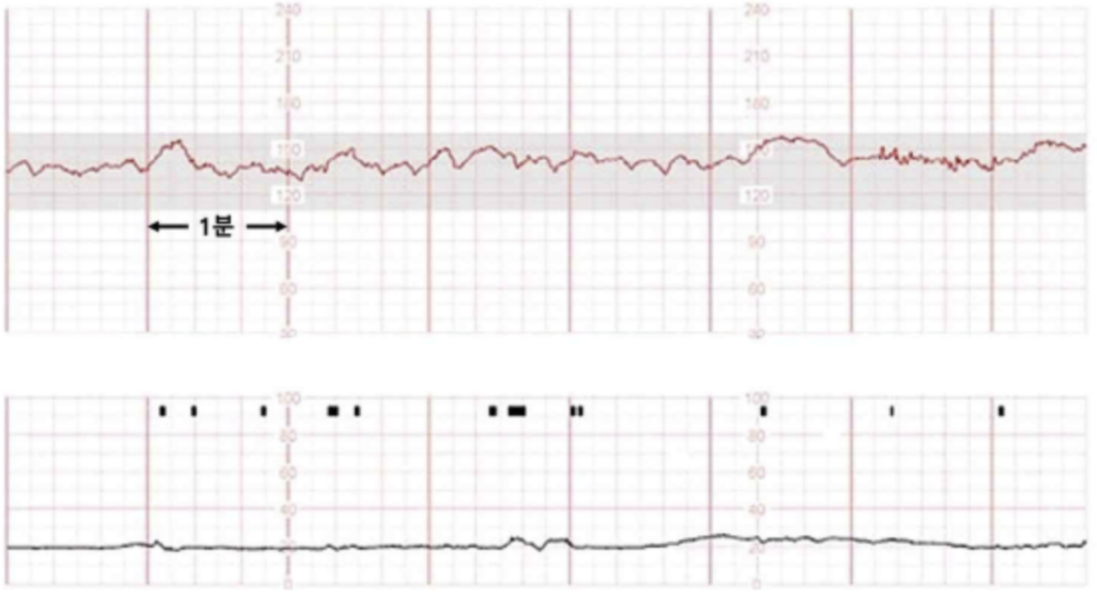

임신 18주인 36세 미분만부가 4시간 전부터 아랫배가 아프고 물 같은 질분비물이 나와서 병원에 왔다. 혈압 120/80 mmHg, 맥박 80회/분, 호흡 20회/분, 체온 36.7°C이다. 골반검사에서 자궁경부는 닫혀있다. 질 안에서 물 같은 소량의 액체가 보이고, 나이트라진 검사 결과는 노란색이다. 초음파검사에서 태아는 둔위, 예측태아몸무게 230 g (50백분위수 223 g), 자궁경부길이 4 cm, 양수와 태반은 정상이고, 태아심박동은 150회/분이다. 자궁수축감시검사 결과이다. 처치는?

Fetal CTG: FHR nl, no uterine contraction

하복부 통증 및 질 분비물을 호소하는 산모의 CTG, 골반검사, nitrazine 검사 결과 양막파수 및 조기진통이 확인되지 않으므로 정상 임신으로 판단 하, 경과관찰한다.

• 산모는 질 분비물 외에 하복부 통증을 호소하였으므로 조기진통 여부 또한 확인이 필요하다. 골반검사 결과 자궁경부가 닫혀있으며 fetal CTG상 자궁수축이 없으므로 조기진통 역시 없는 상태이다.